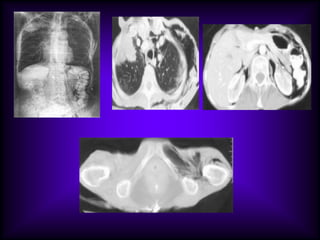

Multiple cysts of metastasis

from squamous cell

carcinoma.

Multiple thick wall cavities from

adenocarcinoma of right lung